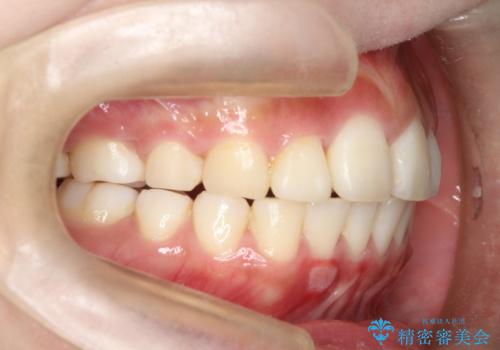

- 上の前歯が出てて、前歯で咬めないとのことで来院されました。

上顎の歯を1本抜歯して、前歯のガタガタと、前方に出ているのを改善する計画としました。

上下の前歯の距離が近くなり、前歯で咬みやすくなり、審美的にも改善できました。